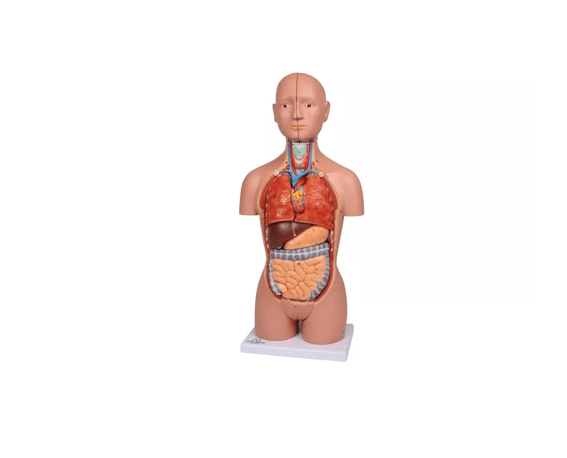

Dieses Torso-Modell in ca. ½ Lebensgröße bietet eine kompakte und dennoch äußerst detailreiche Darstellung der menschlichen Anatomie. Ideal geeignet als Schreibtischmodell, für den Anatomieunterricht oder zur Patientenaufklärung, vermittelt es anschaulich die Lage und den Aufbau innerer Organe – inklusive männlicher und weiblicher Geschlechtsorgane. Die verschiedenen Komponenten lassen sich entnehmen und untersuchen, was das Modell besonders nützlich für den Einstieg in die menschliche Anatomie macht. Lieferung erfolgt auf stabiler Grundplatte inklusive beschrifteter Anleitung.

Modellteile im Überblick:

Grundkörper mit zwei Kopfhälften

Eine Kopfhälfte mit herausnehmbarem Gehirn

Zwei Lungenhälften

Herz (zweiteilig zerlegbar)

Magen

Leber

Darmpaket mit abnehmbarem Blinddarmdeckel

Weibliche Geschlechtsorgane (zweiteilig)

Männliche Geschlechtsorgane (zweiteilig)